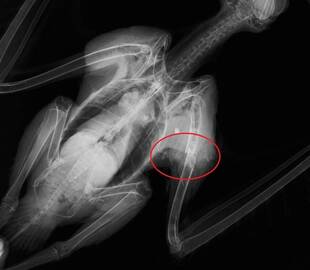

ミゾゴイの骨折